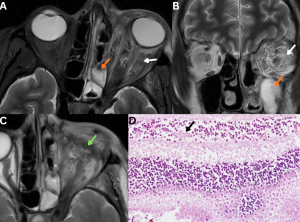

Fig 4: Clinical history:

A 62-year-old diabetic male presented with rapidly progressive left periorbital swelling, vision loss, and ophthalmoplegia.

Figures A & B:

Axial and coronal T2-weighted MRI images demonstrate mucosal thickening within the left ethmoid and maxillary sinuses (orange arrows), with ill-defined T2/FLAIR hyperintensity and fat stranding in the left orbital fat (white arrows), consistent with orbital extension.

Figure C:

Axial T2-weighted MRI image demonstrates post-enucleation changes of the left globe (green arrow).

Figure D:

Histopathology demonstrates broad, pauciseptate fungal hyphae infiltrating the retina (black arrow), confirming mucormycosis.